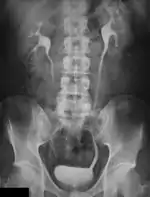

A selection of clinical applications of Digital Radiography are described in this chapter. General Radiography, being one of the mainstays of Diagnostic Radiography, has changed from a film-based imaging process to one based on digital technologies. The impact of these changes in terms of radiation dose and image quality are discussed in this chapter. Specialised applications such as Mammography, Digital Subtraction Angiography, C-Arm Computed Tomography, Multi-Detector CT, Dual-Energy Radiography and Image Fusion are also considered.

General Radiography

Digital image receptors have been increasingly applied in general radiography since the turn of the century. Early studies indicated its superior image quality relative to film/screen technology in skeletal radiography[1][2]. On this basis, refinements of exposure technique have also occurred[3][4][5][6]. Furthermore, dose comparisons with traditional radiography and various forms of Computed Radiography (CR) with direct and indirect Digital Radiography (DR) have been made[7][8][9]. In addition, the performance of digital image receptors for fluoroscopic applications has also been investigated[10].